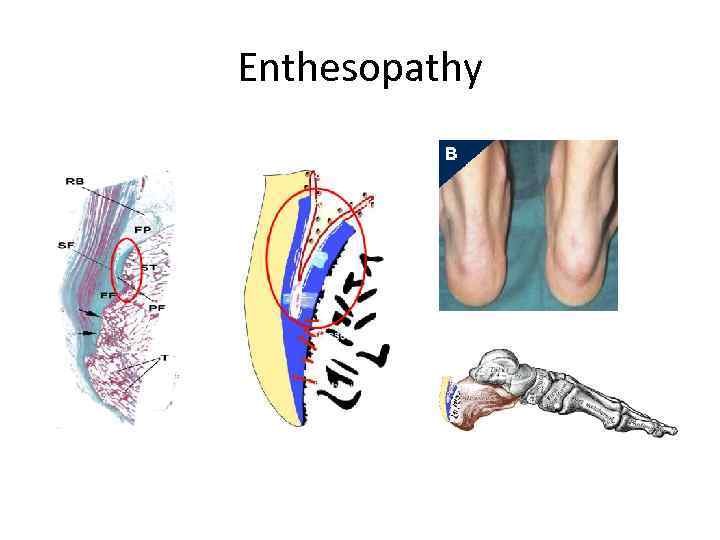

Enthesopathy

Enthesopathy

Enthesopathy